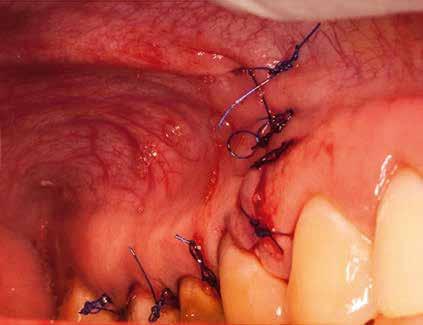

A beavatkozás során helyi érzéstelenítésben teljes vastagságú mucoperiostealis lebenyt képeztünk, és a sablon segítségével bejelöltük a preparálandó csontablak határait. Az ablak széleinek megfelelően Piezotome CUBE LED kézi-darabbal (ACTEON) a kortikális teljes vastagságában vágást ejtettünk, majd az így kapott csontlemezt (ablakot) eltávolítottuk (1. e–h. ábra), és ezt követően steril fiziológiás sóoldatba helyeztük. A rezekció elvégzését követően (1. i. ábra) a mezialis csatornákat ultrahangos eszközök segítségével (NSK) retrográd irányból preparáltuk, majd az így kialakított mélyedésbe retrográd gyökértömést készítettünk. A tömés anyagául az EndoSequence BC RRM Fast Set Putty-t (Brasseler) választottuk. A tömés elkészítését követően a csontablakot visszaillesztettük, és a stabilizálása érdekében a vágásoknak megfelelően kialakult résekbe kollagén szivacsokat (Collagen Tape, Zimmer Biomet) helyeztünk (1. j-k. ábra). A lebenyt 6/0-s Prolene varratokkal (Corpaul) rögzítettük.

A kétéves kontroll során elvégzett klinikai és radiológiai vizsgálat (CBCT-felvétel) a periapicalis elváltozások megszűnését és a corticalis csontállomány tünet- és szövődménymentes gyógyulását